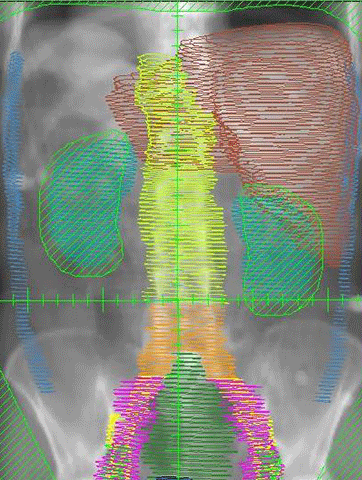

膵臓がん患者のクリス・ジョセフ

•腹部の不快感はステージIIIの膵臓がんの診断につながります

•新しい腫瘍内科医による遺伝子検査は、マイクロサテライト不安定性(MSI-Hign)を示しました

•キイトルーダ(一般名ペンブロリズマブ)による治療